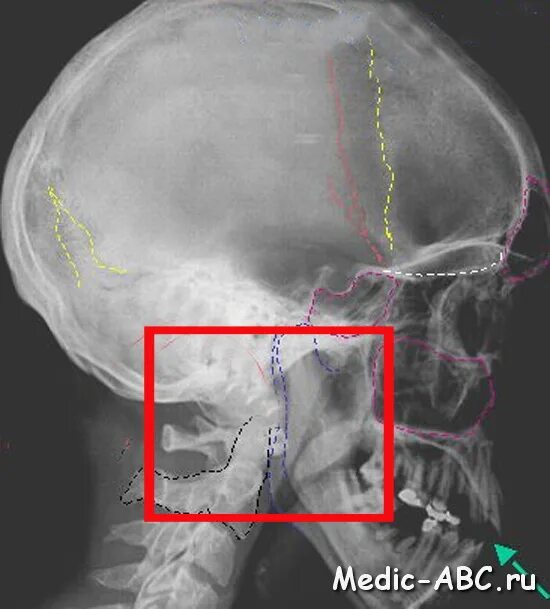

Оскольчатый перелом черепа